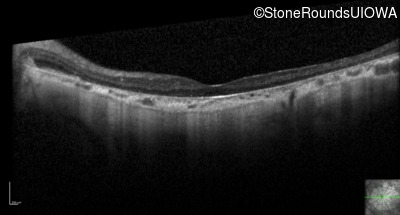

Optical Coherence Tomography - Right - 10/200

Exemplar / OCT Stack